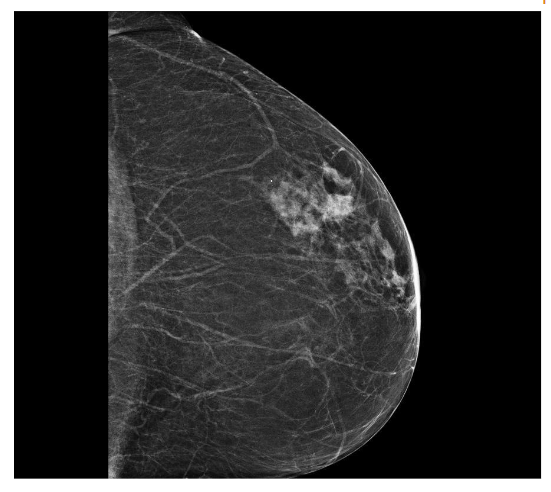

In September 2019, a 69-year-old woman presented to the emergency department of the University Hospital Città della Salute e della Scienza – Turin (Italy), reporting extreme fatigue and dyspnea. She had no comorbidities except for a medical history of papillary thyroid cancer, treated with thyroidectomy and radiotherapy 13 years before. Her complete blood count revealed anemia, thrombocytopenia, and leukocytosis (Hb: 7.8 g/dL, PLT: 37 × 109/L, WBC: 45 × 109/L), while her physical examination was normal. The bone marrow smear showed 84% of blasts with myeloid immunophenotype (CD45, CD13, CD33, HLA-DR, lysozyme, CD36, CD64, CD11bc, partial CD14, and CD4 positive), molecular biology showed NPM1 mutation and FLT3-ITD positivity, while karyotype was normal (46, XX, 20/20). Consequently, a diagnosis of FLT3-ITD+ and NPM1 mutated t-AML was made. Induction chemotherapy was started with CPX-351 (liposomal daunorubicin 44 mg/m2 and cytarabine 100 mg/m2), obtaining CR with a 3-log NPM1 reduction (0.177). She was consolidated with CPX-351 (liposomal daunorubicin 29 mg/m2 and cytarabine 65 mg/m2 day 1 and 3), remaining in CR with persistent low level of measurable residual disease (MRD), NPM1 0.34. Meanwhile, we found a suitable HLA matched donor, but the patient refused the transplant procedure. Thus, we decided to start off-label azacitidine as maintenance therapy (50 mg/m2 subcutaneous daily for 5 days, every 28 days). Maintenance therapy was globally well tolerated, and the patient experienced only positivity for COVID-19 without need of hospitalization or additional care. She remained in CR with persistent MRD in BM (NPM1 0.044 after 12 cycles). During the fifteen course (May 2021), we found a palpable right mammary nodule on physical examination, confirmed on ultrasound, with a diameter of 18 x 11 mm.

We stopped azacitidine and we promptly biopsied the nodule with a diagnosis of breast infiltration by AML blasts carrying the NPM1 mutation. CT scan and PET of chest, neck and abdomen were negative, and BM evaluation showed 1% blasts, with NPM1 0.044. The FLT3-ITD mutation resulted positive on breast cells while negative on medullary blasts. Thus, concluding for extramedullary relapse of AML FLT3-ITD mutated, we decided to start gilteritinib as single agent, at a dose of 120 mg daily. After 30 days, mammary ultrasound showed a reduction in diameter of the nodule.

Myeloid sarcoma (MS), also referred to as extramedullary myeloid infiltration, was first described in 1811 by Burns. Initially, the tumor was called “chloroma” because of its greenish hue, which was later linked to the presence of the MPO (myeloperoxidase) enzyme by King in 1853. The tumor was identified as a mass composed of myeloid blasts, causing disruption in the normal tissue structure. The connection between MS and myeloid leukemia was first established in 1893 by Dock. Histologically, MS consists of immature granulocyte precursors, such as myeloblasts, promyelocytes, myelocytes, and granulocytes. Core biopsy is preferred over fine needle aspiration for the histologic and immunophenotypic evaluation, FISH, PCR, and NGS allows a better understanding of the patient’s prognosis and identification of potential treatment targets. It is observed in 3-8% of adult patients with acute myeloid leukemia. It can occur in the context of intramedullary AML (synchronous extramedullary AML), or in an isolated form with an essentially normal bone marrow (isolated extramedullary AML; also called “nonleukemic” or “aleukemic”), which is usually followed by the development of metachronous intramedullary AML. Its frequency is higher in the post-allo-HSCT relapse setting with about 15% of all post allo-HSCT AML relapses being isolated EMI. While the exact cause of MS development remains unclear, it is thought to involve the migration of leukemia blasts to extramedullary sites, facilitated by specific adhesion molecules found on the blast cell surfaces. Age might influence the presence of MS; most studies have reported a median age at diagnosis ranging from 46 to 59 years, with approximately 52–59% of affected patients being male. Certain genetic features, including trisomy 8, monocytoid differentiation of blasts, MLL rearrangements, as well as CD56 positivity and the absence of CD117 (c-kit), are associated with an increased risk of developing MS in AML. These factors enhance the ability of leukemic cells to migrate to areas beyond the bone marrow. Recent reports have highlighted the frequent occurrence of FLT3 mutations in patients with EMI. FLT3-ITD mutations were the first molecular abnormalities to be identified in MS cells with initial studies detecting the mutation in up to about 30%, which is similar to the frequency noted for typical AML. NPM1 mutations are detected in up to 50% of cases, again comparable to conventional AML. MS in the breast is extremely rare, making up only about 3% of all MS cases, according to a Mayo Clinic study. Due to its infrequency, it is often mistaken for other breast malignancies, such as lobular carcinoma, non-Hodgkin’s lymphoma, or small round blue cell tumors. A recent review by Sharma et al. examined 67 previously reported cases, 66 of which were women and only one was a man. In most instances, breast MS presents as a rapidly enlarging mass, which may affect one or both breasts. Nipple retraction is generally not observed. Right-sided breast involvement is more common than left-sided. In terms of imaging, MS in the breast typically appears as a large, irregular, non-calcified mass with poorly defined, “feathery” margins, a characteristic finding consistent with the mammograms of the patients in the study. FDG-PET/CT at diagnosis, after treatment completion, and at the time of suspected relapse is an important tool that allows for timely adjustments to the management strategy.